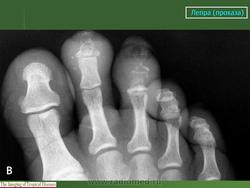

Что касается нервной формы проказы (рис. 216), то наиболее ранним, постоянным и общим рентгенологическим ее проявлением служит остеопороз. IK остеопорозу рано присоединяются явления остеолиза. Иконография (т. е. описание картины) остеолиза дается различными авторами в традиционном для лепрологии стиле в чрезвычайно тонких и кропотливых внешне описательных образах. Здесь преобладают сравнения с общеизвестными предметами, как, например, отточенными кончиками карандаша, шахматными пешками и другими фигурами, кнопками, пуговицами для воротника, запонками, тающими свечами, обсосанными леденцами, столбиками, иглами и т. д. Существенно то, что налицо частичное или полное рассасывание и исчезновение костных элементов без их замещения другой тканью и без продуктивной репаративной реакции. Характерно истончение и укорочение костей, в первую очередь ногтевых фаланг. Рассасывание ногтевой фаланги начинается с ее ногтевого отростка. Структура бугорка становится крупнопористой, ноздреватой. Затем срезается дистальный или боковой край, развивается плоская или вогнутая узура, постепенно увеличивающаяся, а затем и весь ногтевой отросток сходит на нет; обнажается шейка. Основание фаланги рассасывается с одного края или с обеих сторон, иногда и целиком. В дальнейшем без каких-нибудь клинических признаков очередь доходит до фаланг средних и основных, а также пястных и плюсневых костей, с переходом на запястье и предплюсну, порой до полного исчезновения скелета одного, нескольких, многих или всех пальцев.

В локализации этих костных поражений трудно определить какую-нибудь иннервационную закономерность, т. е. связь с тем или иным иннервационным районом, что свойственно всем костным поражениям "а нервнотрофической почве. Если в одних случаях имеется симметричность поражений, то в подавляющем большинстве случаев удивляет именно асимметрия двусторонних поражений. Тяжесть калечения при нервной проказе не находится в прямой связи с длительностью забдлевания.